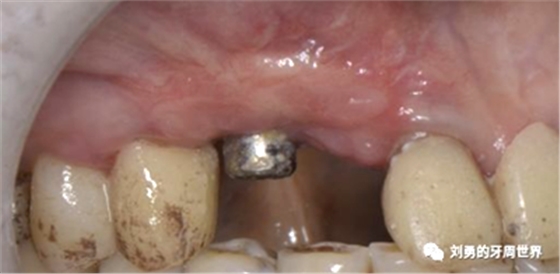

可見右上前牙植體頰側(cè)無附著齦

為了減少取瓣大小,從上腭取厚一點的齦瓣,然后用刀片平行于表皮表面將齦瓣片切成兩個厚度一致的齦瓣,然后進(jìn)行移植,這樣切成的兩個齦瓣一個有表皮,一個沒有表皮是單純的結(jié)締組織。如此的片切可以使齦瓣變成雙倍的大小使用,減少了供區(qū)的取瓣面積。